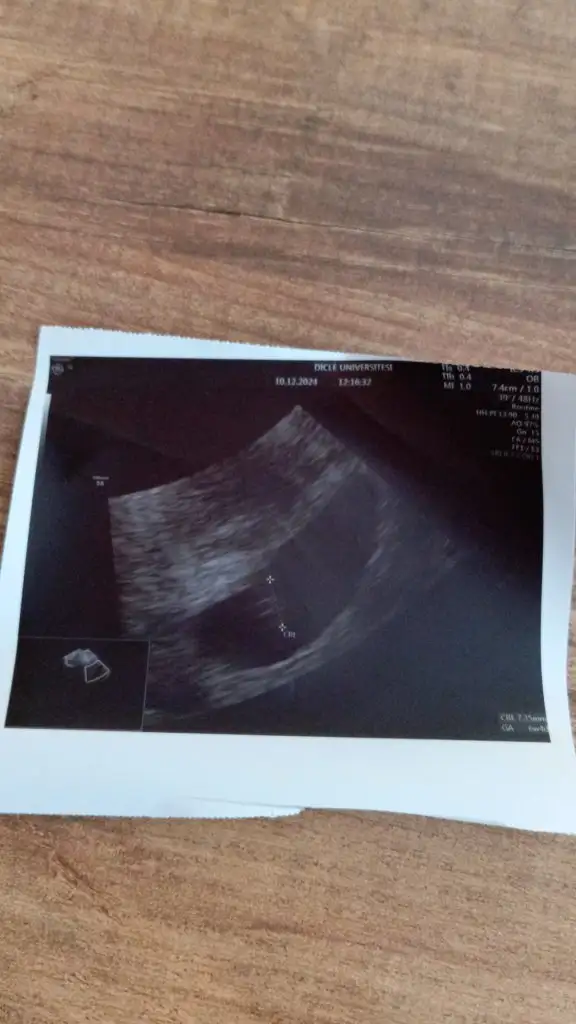

Canım kızlar doktordan çıktım anca yazmaya fırsat buldum çok şükür dediğiniz gibi çıktı bebişi gördüm kalbini de çok az dinletti daha çok küçükmüş 🥹🥹 sat a göre 7+4 ama bebiş 6+4 çıktı o yüzden geçen hafta görmemişiz bu sefer sevinçten gözyaşı döktüm bu da bebişim ilk resmi teyzeleri melegim can melegim can imagination forever imagination forever Niqu Niqu fnd_50 fnd_50 O _okyanus Merve3553 Merve3553 Tikabasa Tikabasa Bezgininsan Bezgininsan M Marryyj